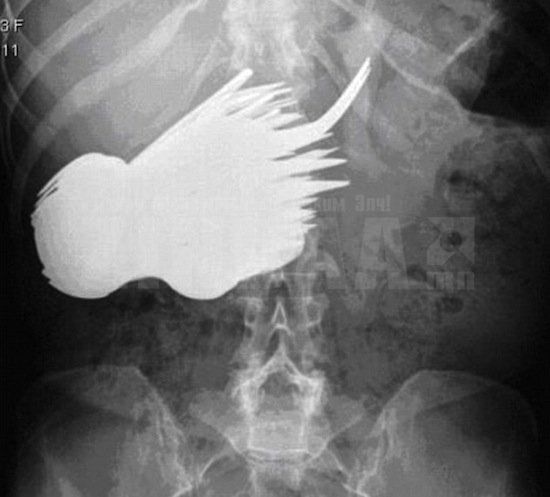

52 настай Холландын иргэн Маргарет эмнэлэгт ирээд ходоод нь өвдөж байгаагаа хэлээд рентген зургаа авахуулжээ. Гэтэл хэвлийд нь том хэмжээтэй цагаан толбо бүхий зүйл илэрсэн байна. Жинхэнэ шок... Түүний дотор 78 ширхэг халбага сэрээ байгаа нь тогтоогдов. Тэр өөрийн эрхгүй л эдгээрийг залгичихдаг байснаа эмч нарт хэлжээ. Тэр олон жилийн турш тэдгээрийг нэг нэгээр нь “идсэн” байна.